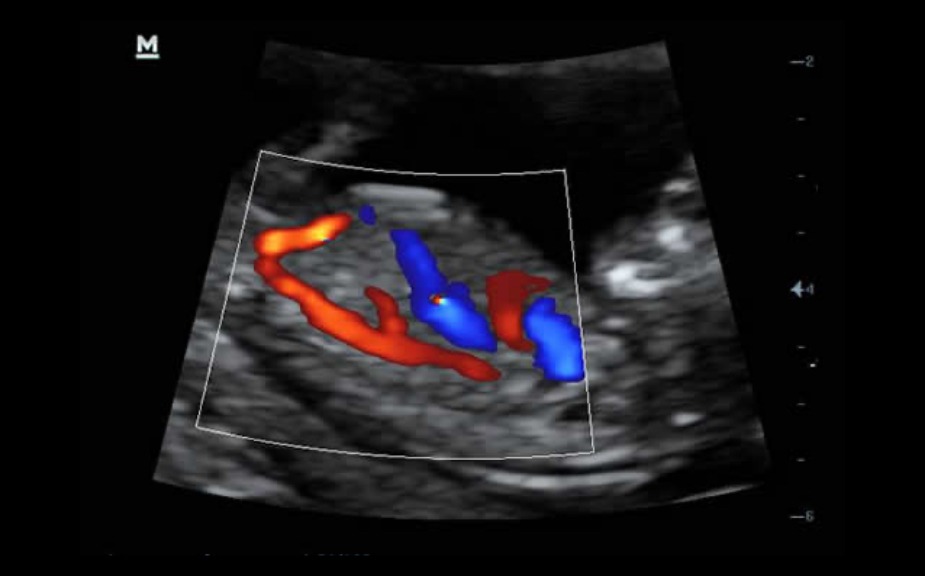

PSH? (Phase Shift Harmonic Imaging)

ImĂĄgenes de armĂłnicos purificados con desplazamiento de fase para una mejor resoluciĂłn de contrastes que proporciona imĂĄgenes mĂĄs nĂtidas con excelente resoluciĂłn y menos ruido.

iBeam?

Permite el uso de varios ĂĄngulos de exploraciĂłn para formar una sola imagen, lo que ofrece una mayor resoluciĂłn de contrastes y una mejor visualizaciĂłn.